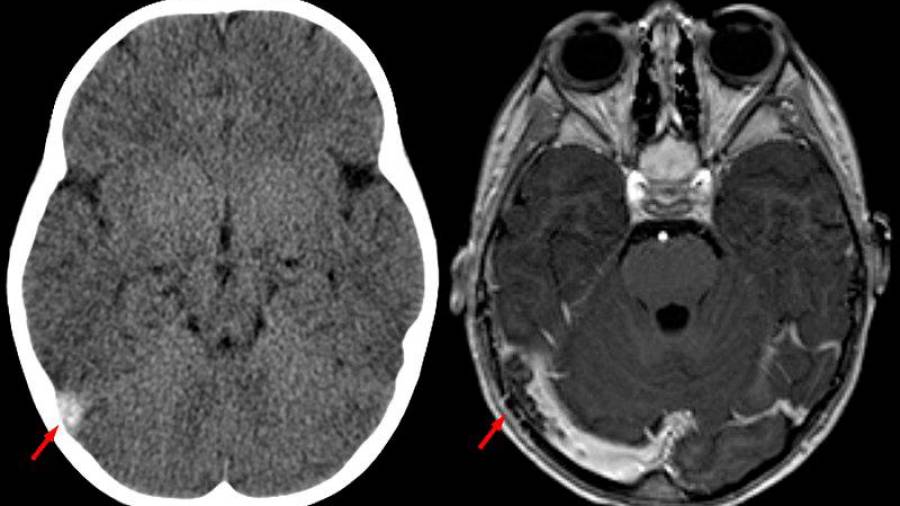

Ha demostrado ser un método confiable para investigar la estructura de las venas cerebrales, con una sensibilidad reportada del 95% (7,8). La CTV puede mostrar un defecto de llenado dentro de la vena o del seno, el clásico signo de “delta vacío”, en el que se presenta una hipodensidad central (Figura 2).